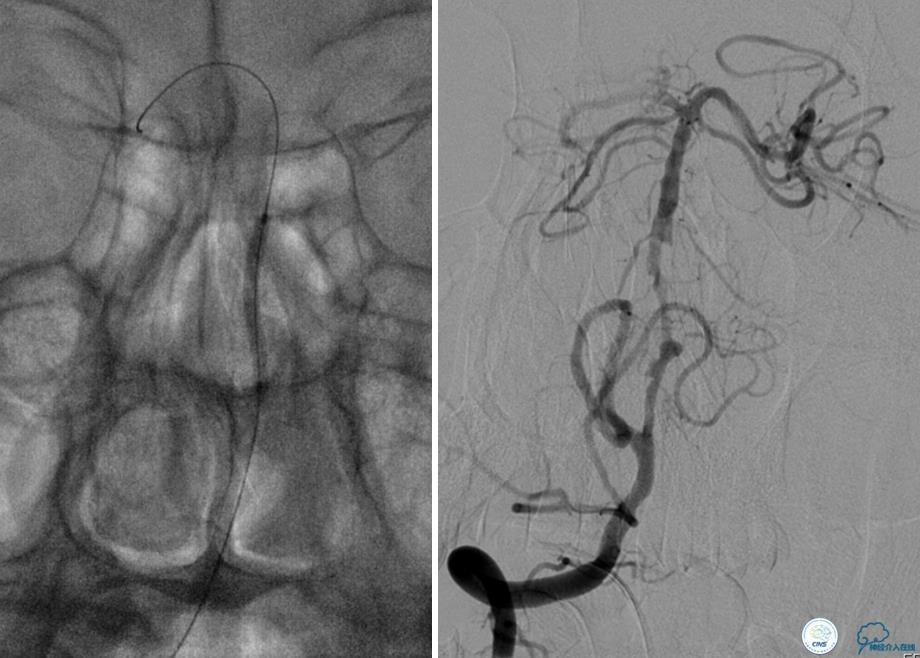

病例5

患者:49岁男性,左侧偏瘫1个月,药物治疗、康复训练效果不好,转我院,肌力0~1级。

core-clilnical明显不匹配,是介入开通的合适患者。

造影评价血管、判断闭塞段,微导丝小心穿过闭塞段,微导管造影,交换技术,球囊扩张,Enterprise支架。在后扩张时导丝刺破M3段血管,蛛网膜下腔出血(SAH)。

微导管进入破裂血管,栓塞弹簧圈1枚,出血停止,结束手术。继续双抗,术后2天肌力2级,神经功能恢复明显加快。

术后即刻和6天后CT,患者无明显临床症状。

半年后复查造影,无支架内再狭窄,可见弹簧圈,患者恢复至自己柱杖行走。